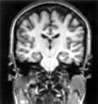

A patient with classic temporal lobe epilepsy shows a damaged right hippocampus in this MRI slice, face forward, parallel with the plane of the face. A well-formed infolding of the hippocampus is seen on the right side of the picture and only a fuzzy remnant on the left side of the picture.

- In many cases the seizures originate in a small area deep in the temporal lobe on one side of the brain.

- Resection, or removal of this area, results in complete freedom from seizures in more than 70 percent of patient